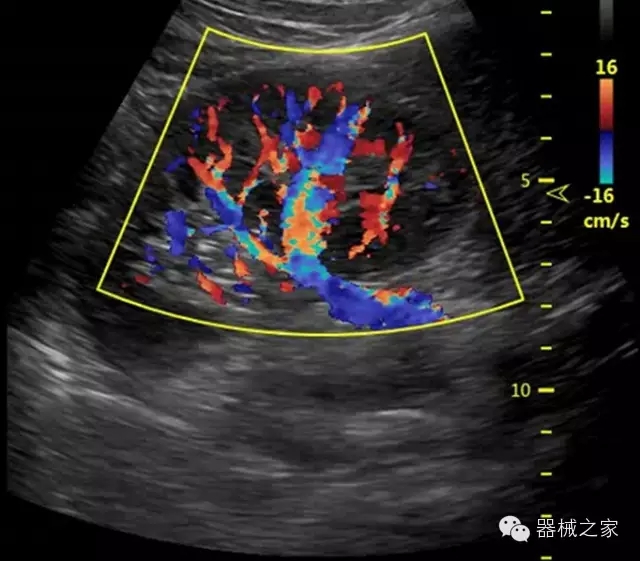

臨床圖片賞析

產(chǎn)品特點

優(yōu)異的成像技術(shù)

·亞陣元技術(shù):獨有的亞陣元技術(shù),對獨立晶片做二次切割,減少旁瓣偽像,增加臨床診斷的準(zhǔn)確性;

·μ-Scan微米成像技術(shù):開立獨有的μ-Scan技術(shù),還原出真實細(xì)膩、層次對比優(yōu)異的二維圖像;

·倒相諧波成像技術(shù):倒相諧波技術(shù)在去除基波信號的基礎(chǔ)上獲取兩倍二次諧波信號,提高組織圖像的對比分辨力;

·智能微血流成像技術(shù):智能微血流捕捉技術(shù)可以提取出隱藏在背景噪聲中的弱血流信號,大大提高低速血流的敏感性;

全面的臨床解決方案

超聲科常規(guī)領(lǐng)域應(yīng)用

·移植S40高端臺式彩超高端平臺技術(shù),滿足超聲科腹部、淺表、婦產(chǎn)科、心血管、肌骨等應(yīng)用,提供超聲科完美解決方案;

·實時的彈性成像技術(shù):提高了小器管(乳腺,甲狀腺、淺表軟組織腫瘤等)疾病鑒別診斷;

·IMT血管內(nèi)中膜自動測量:為血管性疾病評估提供了有效的評估手段;

·心功能綜合指數(shù)(TEI指數(shù)):用于左、右心室整體心臟收縮舒張功能評估的測量方法;

·全方位可調(diào)M型:有利于更好的觀察心腔大小及室壁階段性運動的異常情況;

·組織多普勒成像(TDI):TDI可定量評價心肌運動,判斷是否有局部病變,還可評價早期的舒張功能;

·高效3D/4D成像技術(shù):高速的4D幀頻,豐富的3D成像模式,智能斷層切片功能;

POC領(lǐng)域解決方案

·外觀小巧;

·穿刺增強(qiáng)技術(shù):可有效提高進(jìn)針區(qū)圖像分辨率,提高進(jìn)針亮度,全面提高一次性穿刺的成功率;

全面的術(shù)中探頭解決方案

·小凸探頭:開放性手術(shù),實時監(jiān)測病灶位置,提高手術(shù)成功率,可應(yīng)用于麻醉科、肝膽外科、腫瘤外科、神經(jīng)外科、泌尿外科等手術(shù);

·L型線陣探頭:高分辨率圖像,清晰顯示病灶位置,提高手術(shù)成功率,可應(yīng)用于麻醉科、胸外科、肝膽外科、腫瘤外科、神經(jīng)外科、泌尿外科等應(yīng)用;

·MPTEE:經(jīng)食道探頭術(shù)中監(jiān)測,可測量心臟前負(fù)荷(左室舒張末期大小、右房大?。?、心排血量、后負(fù)荷、收縮功能、室壁運動分析、肝靜脈血流(與中心靜脈壓相關(guān))等,術(shù)后還能及時評估手術(shù)效果評估;

·獨有的大角度及實時溫控技術(shù),能同一切面顯示宮頸及宮體,有效減低了患者的痛苦,及保護(hù)粘膜保證了醫(yī)療安全;

高效的人機(jī)工程學(xué)設(shè)計

·15‘’高清醫(yī)用顯示器;

·內(nèi)置雙探頭接口;

·可升降臺車,1拖3探頭擴(kuò)展器;

·m-Tuning一鍵優(yōu)化;

·粵食藥監(jiān)械(準(zhǔn))字20132230491